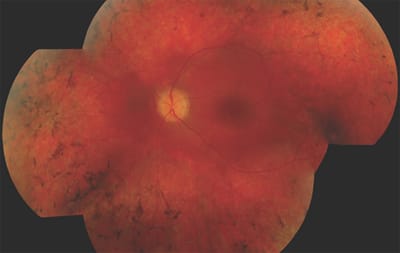

The product of a nonconsanguineous marriage, Patient 1 was born after a normal pregnancy and normal delivery. The parents noted roving eye movements, and the child appeared to be nonresponsive to light stimuli. He was otherwise healthy. On funduscopy, a normal optic disc with mild attenuation of the vessels was observed. A tapetoretinal reflex was visible without any other abnormalities. ERG testing showed undetectable cone and rod responses. There were no systemic abnormalities, and he had normal intelligence. His left fundus at 28 years old is shown in Figure 3.

Figure 3. At age 28 years, the retina of the left eye of patient 1 (CEP290 mutations) shows a relatively normal optic disc, narrow arterioles and a normal macula. The periphery shows hypopigmentation with intra-retinal bone spicules.

Patient 1 has LCA due to mutations in CEP290, which encodes a centrosomal protein. The CEP290 gene functions in cilia, and therefore its expression is not confined solely to the eye. Because of the ubiquitous expression of this gene, mutations are correlated with a phenotypic spectrum, ranging from nonsyndromic LCA to more complex diseases, such as Joubert syndrome (JS; MIM# 213300), Senior-Loken syndrome (SLS; MIM# 266900), Meckel-Grüber syndrome (MKS; MIM# 249000) and Bardet-Biedl syndrome (BBS; MIM# 209900).

The CEP290-related ocular phenotype is characterized by poor VA, typically in the range of LP (though with some LP-negative patients), high hyperopia and limited fundus abnormalities present in early childhood. Throughout life, the macula remains relatively spared, with an epiretinal membrane present in most patients. Later in life, mild attenuation of the vessels may be observed, with a marbleized and/or salt-and-pepper fundus, which ultimately develops into a progressive outer retinal atrophic aspect in the midperiphery. Autofluorescence imaging may show a hyperautofluorescent ring around the central macula.4